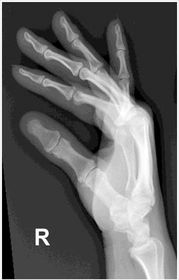

| AP Thumb | metacarpals overlapping thumb |

| Oblique Thumb | slightly overrotated foreshortened distal phalanx |

| Lateral Thumbs | should be concave to one side only and straight on the other images are not truly lateral |

| PA Hand | distal phalynxes are bent flatten hand to true PA *should be equal concavity on all digits* |

| PA Hand | obliqued - fingers are not equally concave on both sides distal metacarpals are overlapped |

| Oblique Hand | Overly obliqued - metacarpals superimposed joint spaces closed - fingers bent |

| Oblique Hand | MCP joints superimposed - fingers too close together *underexposed |

| Oblique Hand | joint spaces closed hand overly obliqued MCP joints superimposed |

| Fan Lateral Hand | phalanges are superimposed and not well visualized patient's hand is externally rotated |

| Fan Lateral | patient's 2nd digit is bent - closed joint space hand is internally rotated |

| Fan Lateral | patient's metacarpals are not superimposed - hand is externally rotated distal phalanx's are bent - joint spaces closed not truly lateral |

| PA Hand | ANATOMY: entire hand including 1'' of distal radius and ulna CRITERIA: equal concavity on either side of digits digits separated with no superimposition open joint spaces POSITIONING: CR perpendicular @ 3rd MCP joint |

| Oblique Hand | ANATOMY: entire hand including 1'' of distal radius and ulna CRITERIA: digits more concave to one side minimal overlap of 3rd-5th metacarpal shafts separation of the 2nd and 3rd metacarpals POSITIONING: CR perpendicular @ 3rd MCP joint |

| Lateral Hand | ANATOMY: entire hand including distal 1'' of radius and ulna superimposed CRITERIA: metacarpals and distal radius/ulna are superimposed thumb is free of superimposition *thumb in lateral position* open joint spaces POSITIONING: CR perpendicular @ 3rd MCP joint LAT Extension: foreign body localization LAT Flexion: phalanges |